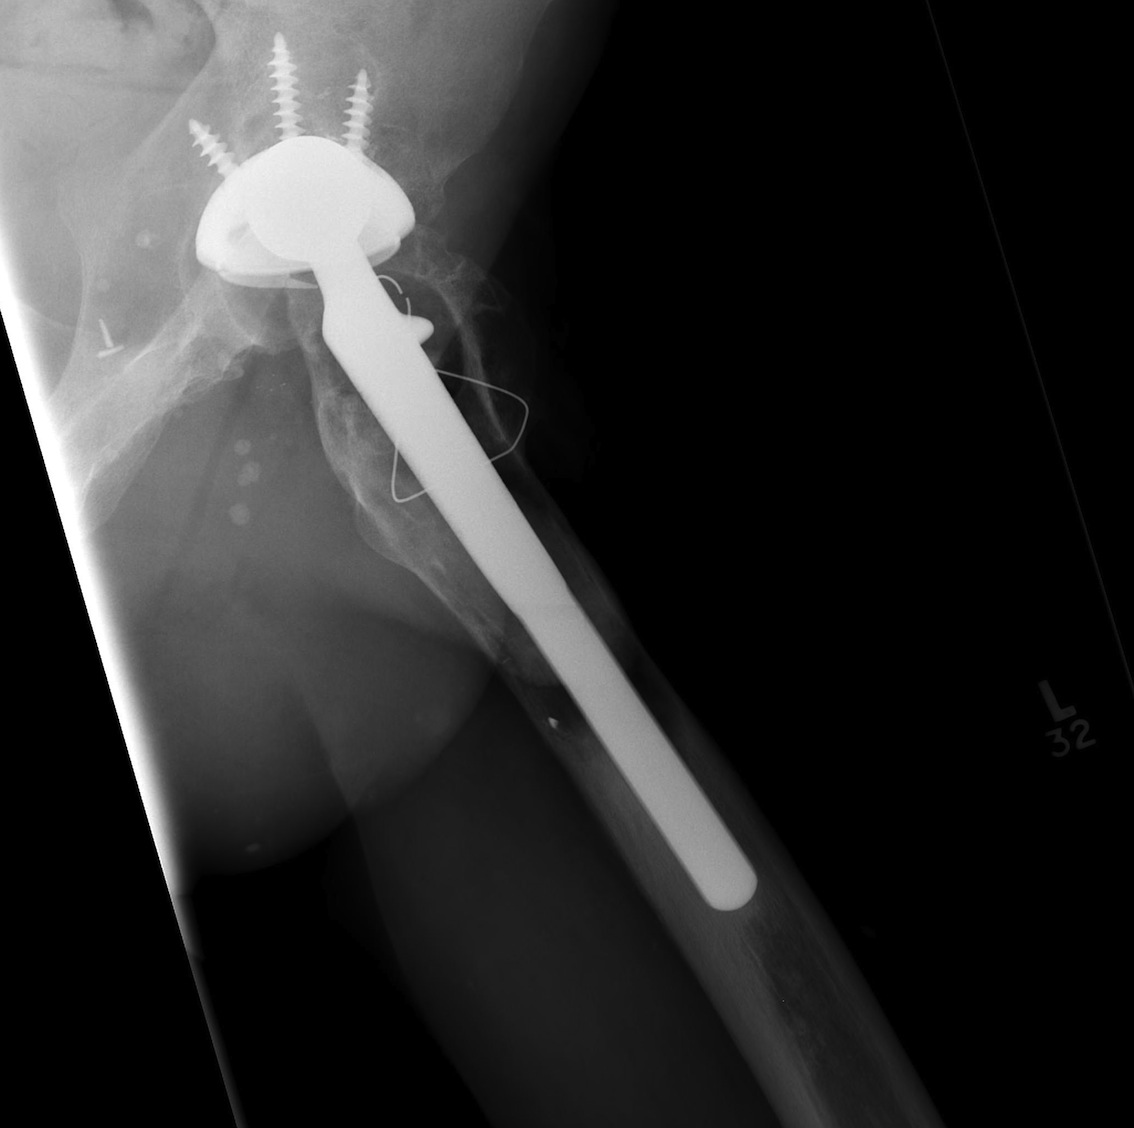

C. Proximal Femoral Replacement / Tumour prosthesis

D. Bulk Structural Proximal Femoral Allograft

Technique

- desired stem cemented into allograft

- press fit distally into host femur

- step cut graft host junction

- secure cerclage wire and onlay cortical strut

- proximal host bone wrapped around allograft with ABD preservation

- very important – abductor mechanism must be secured and protected